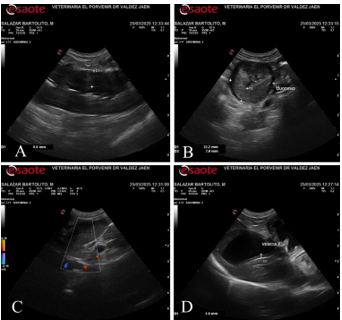

El 25 de marzo el paciente regresó por empeoramiento clínico. En el ultrasonido se evidenció en la porción descendente del duodeno, posterior a su flexura inicial, un engrosamiento severo y concéntrico de la pared con pérdida de la estratificación, con un espesor de 0 ,70 cm que se extendía desde el epigastrio derecho hasta la región craneal de la vejiga urinaria con contenido luminal de patrón fluido. En el resto del intestino no se observaron irregularidades en la superficie de la pared, ni engrosamiento de la misma. La estratificación se encontraba conservada, al igual que el peristaltismo. Se identificó linfonodos yeyunales reactivos (Figura 1 A, B y C). La vesícula biliar se encontraba pletórica y presentaba engrosamiento de la pared de 0,19 cm, hipoecogénica y con la mucosa levemente irregular. Además, presenta contenido anecogénico con barro biliar escaso en zona declive (Figura 2 D).

El segundo ultrasonido se realizó el día 31 de marzo, luego de la segunda intervención quirúrgica; en este se observó, en la porción descendente del duodeno un engrosamiento severo y concéntrico de la pared con pérdida de estratificación, con un espesor de 0,65 cm que se extendía en el mesogastrio derecho relacionada al riñón, con un contenido de patrón fluido, similar a la imagen obtenida en el primer estudio ultrasonográfico. El resto del intestino presentaba un aspecto corrugado, pero sin engrosamientos, conservando la estratificación y el peristaltismo. Se identificó linfonodos yeyunales reactivos y signos claros de peritonitis (Figura 3).

Ecográficamente las lesiones fueron principalmente focales, aunque no siempre se pudo estimar su longitud. Todos los perros presentaron engrosamiento de la pared gastrointestinal, algunos presentaron lesiones circunferenciales; otros mostraron engrosamiento focal de la curvatura mayor del estómago y una masa excéntrica en el colon. En todos los casos hubo pérdida del patrón normal de capas de la pared intestinal. En la mayoría de los perros, la pared engrosada era uniformemente ecogénica, de moderadamente a casi anecoica, con un margen mucoso hiperecogénico. Algunos incluso presentaron ganglios linfáticos regionales agrandados, con apariencia hipoecoica o de ecogenicidad mixta.

Entre los diagnósticos diferenciales ecográficos de las enfermedades gastrointestinales inflamatorias se suele incluir: neoplasias, gastropatía urémica, enteropatía inmunoproliferativa, enteritis linfoproliferativa, linfangiectasias. No obstante, las lesiones causadas por pitiosis suelen asemejarse más a neoplasias que a inflamaciones propiamente dichas, debido a la pérdida de estratificación de los tejidos y a la presencia de agrandamiento ganglionar regional. Pese a lo sugerente, la ultrasonografía solo aporta imágenes presuntivas acortando el abanico de patologías responsables del cuadro (Graham et al. 2000).